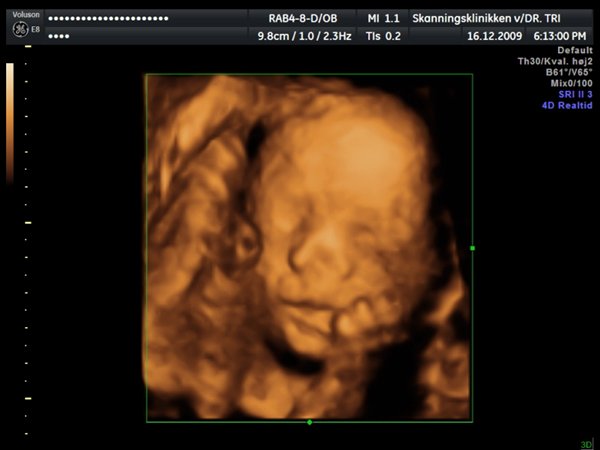

Ja, så var vi til 3D scanning med Ida igår. Og hvad kan jeg sige andet end hun er en meget træt pige

Jeg tror vi talte hun gabte mellem 10 og 11 gange under hele scanningen. Derudover havde hun meget travl med at gemme sig bag sine hænder som hun hele tiden åbnede og lukkede så det så ud som om hun vinkede

Billederne blev ikke så gode som jeg havde håbet, for lige som sin bror ligger hun meget tæt på moderkagen og med navlestregnen forand hovedet. Men de er ok, vi kan da se at hun ser sund og rask ud og at hun trives derinde.

Vedhæftede fotos (klik for at se i fuld størrelse)